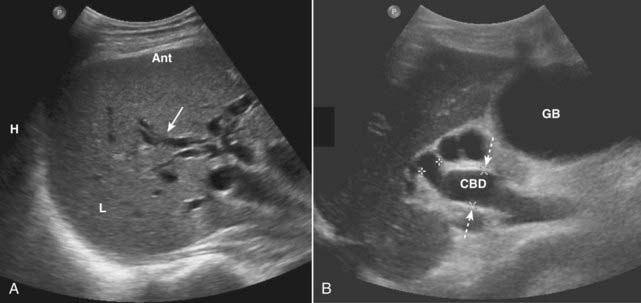

image Ultrasound plays a key role in evaluation of the intrahepatic and extrahepatic bile ducts and pancreatic duct. The intrahepatic biliary radicals drain into the left and right hepatic ducts, which join to form the common hepatic duct (CHD). Where the cystic duct from the gallbladder joins the CHD is the origin of the common bile duct (CBD), which drains either within or adjacent to the head of the pancreas via the ampulla of Vater into the second portion of the duodenum. The CBD lies anterior to the portal vein and lateral to the hepatic artery in the porta hepatis (Fig. 19-7).

Figure 19-7 Normal common bile duct, portal vein, and hepatic artery, sagittal view.

The common bile duct (CBD) measures 3 mm (normal <6 mm). The solid white arrow points to the hepatic artery, seen on end. The portal vein (PV) is posterior to the common duct, and the inferior vena cava (IVC) is seen posterior to the portal vein. The pancreas (P) is anterior to the CBD.

imageThe CHD and proximal CBD can be visualized normally on virtually all ultrasound studies of the right upper quadrant. The CHD measures no more than 4 mm (inner wall to inner wall) and the CBD measures no more than 6 mm in diameter. The pancreatic duct measures <2 mm.

image Normal intrahepatic bile ducts are not visible. When the CBD is obstructed, the extrahepatic ducts dilate before the intrahepatic ducts. Over time, both the intrahepatic and extrahepatic ducts will be dilated (Fig. 19-8).

image Causes of bile duct obstruction include gallstones, pancreatic carcinoma, strictures, sclerosing cholangitis, cholangiocarcinoma, and metastatic disease.

Figure 19-8 Dilated intrahepatic and extrahepatic ducts in two different patients, sagittal images.

A, The intrahepatic (L = liver) biliary ducts are normally not visible by ultrasound. In this case, they are dilated (solid white arrow) from obstruction by a pancreatic carcinoma (not shown). B, The CBD is dilated at 15 mm (dotted white arrows) and the gallbladder (GB) is distended from an obstructing stone (not shown).